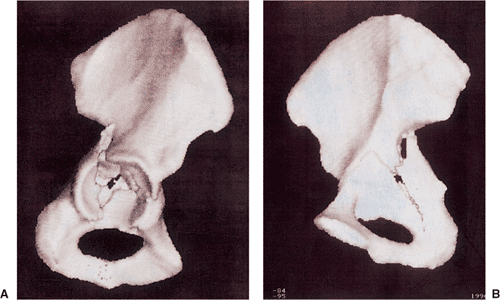

The eventual universal availability of high-quality three-dimensional

CT reconstructions may eliminate much of the mystery associated with

the radiographic interpretation of acetabulum fractures (Fig. 41.7). However, except for the AP

Figure 41.7.

Three-dimensional CT. The fracture as deduced by evaluation of the plain x-rays and two-dimensional CT is shown fairly clearly. An overall appreciation of the fracture pattern is provided. However, there is some loss of definition, especially of the quadrilateral-plate fracture involvement. |

accident, sustaining an atypical T-shaped fracture of the acetabulum

with intra-articular comminution (Figs. 41.46, 41.47 and 41.48).

Figure 41.48. Preoperative three-dimensional CT, showing the external (A) and endopelvic (B) aspects. An atypical T-shaped pattern with intra-articular comminution is demonstrated.